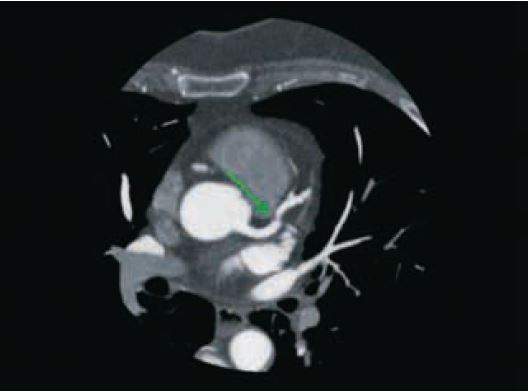

Сканування з низьким кВ генерує менше фотонів для заданого струму трубки і традиційно не застосовується для пацієнтів з високим ІМТ через погане співвідношення сигнал/шум у баріатричних пацієнтів зі звичайними системами детекторів тепер є нашою стандартною технікою КТ-ангіографії у пацієнтів з ІМТ до прибл. 35. У результаті ми змогли зменшити об’єми контрасту приблизно на 40% у цих пацієнтів, значно зменшивши ризик нефропатії, спричиненої контрастом. Крім того, тепер ми можемо набагато безпечніше проводити обстеження з ультранизькими дозами контрасту у пацієнтів із порушенням функції нирок (мал. 4-6).

Pис. 6 ТЕЛА та розшарування аорти можна виключити в одній ротації як правило, при <1 мЗв. 30 мл ніопаму 370 при 3 мл/с.